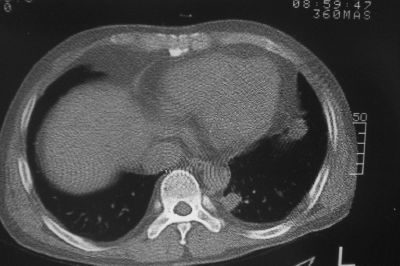

标题: CT10574:男 50岁胸部CT请会诊!

患者 男 50岁 无痛性咯血3天,无其他不适.

左下肺结节状软组织密度影,边缘有毛刺,考虑周围型肺癌。

1 左肺下叶基底段见两结节软组织密度灶, 肺窗边缘见有毛刺征像, 不能排除占位. 2 建议结合临床治疗一周后ct随访在看其结果.

临近胸膜增厚,病变周围肺不清,稍有分叶。结节密度略高,肺、纵隔窗差异不大,肺癌待排。前方还有一个

1 左肺下叶后基底段见结节软组织密度灶,周围见毛刺,建议抗炎后复查,警惕周围型肺癌。

2 心包积液。

左下肺结节状软组织密度影,一个边缘有卫星病灶,邻近胸膜增厚.另一个有毛刺.心影周围水样密度影环绕.考虑:

1.肺癌可能.肺tb待排.

2.左侧胸膜增厚.心包积液.